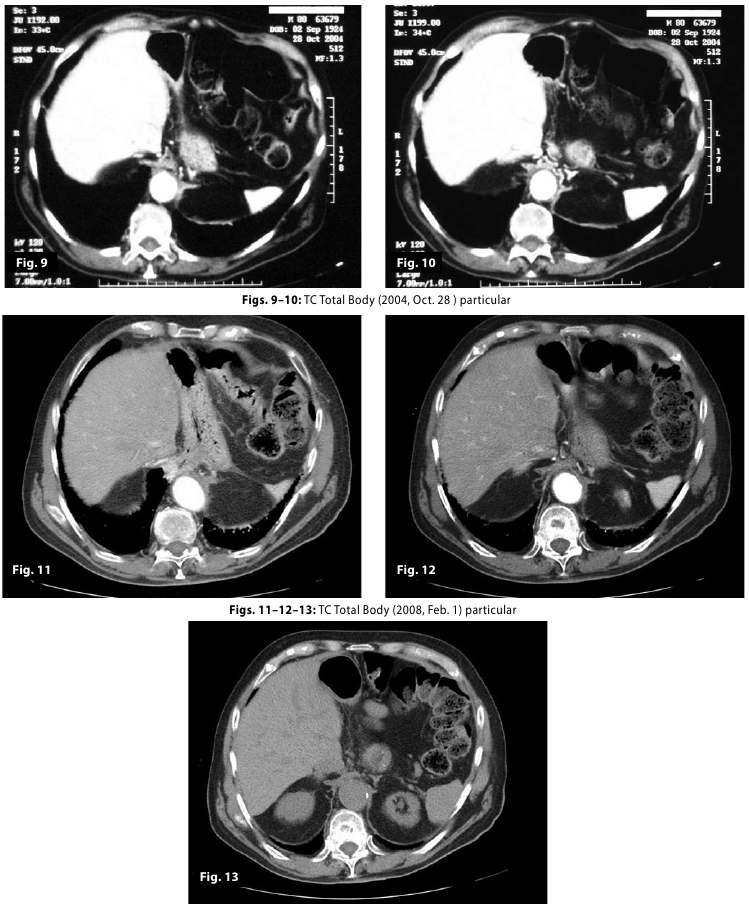

Figure11-12-13

Figure9-10-11-1...